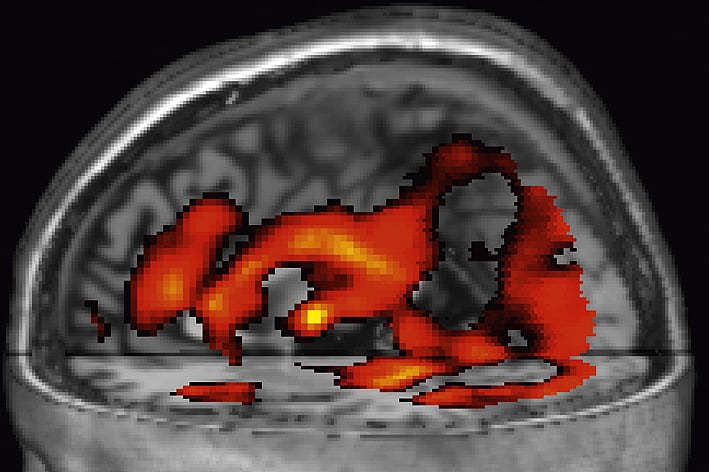

Die Entwicklung der funktionellen Magnetresonanztomografie (fMRT) erlaubt es heutzutage, sexuelle Präferenzen genau dort zu messen, wo sie entstehen - im Gehirn. Die Methode macht die Aktivität im menschlichen Denkorgan in Form von dreidimensionalen Bildern sichtbar. In einer ersten Studie von 2006 hatten meine Kollegen und ich Männer und Frauen sowohl homo- als auch heterosexueller Orientierung untersucht. Eine kurze Darbietung von Nacktbildern löste bei ihnen immer dann eine Aktivität im Belohnungssystem und in Teilen der motorischen Hirnrinde aus, wenn die abgebildeten Genitalien der sexuellen Orientierung der Probanden entsprachen.

Ein Team um Boris Schiffer von der Universitätsklinik Essen konnte 2008 in zwei Studien zeigen, dass auch bei Pädophilen Teile des Belohnungssystems durch Nacktbilder von Kindern stärker aktiviert werden als durch Bilder von Erwachsenen. Insbesondere im Nucleus caudatus und in der Substantia nigra zeigten sich sowohl bei homosexuell als auch heterosexuell veranlagten Pädophilen Aktivierungsunterschiede.

Weiteren fMRT-Studien zufolge kommt es auch auf andere Hirnbereiche an; dennoch lassen sich die meisten Untersuchungen recht gut auf einen Nenner bringen: Entspricht ein Bild der sexuellen Präferenz des Betrachters, feuern vermehrt Neurone im Belohnungssystem - ganz gleich ob der Untersuchte heterosexuell, homosexuell oder pädophil ist.